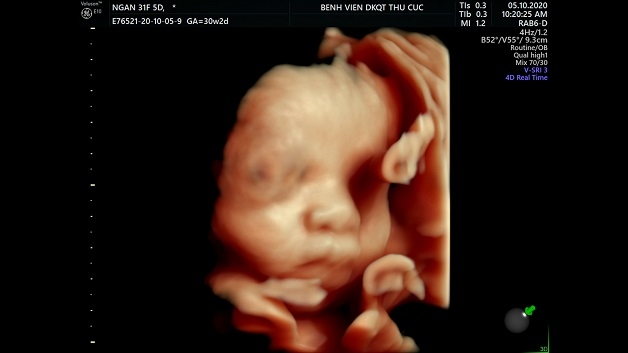

Những mốc siêu âm thai nhi cơ bản mẹ bầu không nên bỏ qua

Hiện nay, siêu âm thai nhi chính là một trong những phương pháp phổ biến nhất, giúp bác sĩ có thể theo dõi sát sao sức khỏe của mẹ và bé. Việc siêu âm định kỳ này còn giúp bác sĩ phát hiện sớm những bất thường ở trẻ, từ đó đưa ra phương pháp xử lý kịp thời. Trong bài viết này, chúng tôi sẽ tổng hợp các mốc siêu âm thai cơ bản, quan trọng mà mẹ bầu không nên bỏ qua.